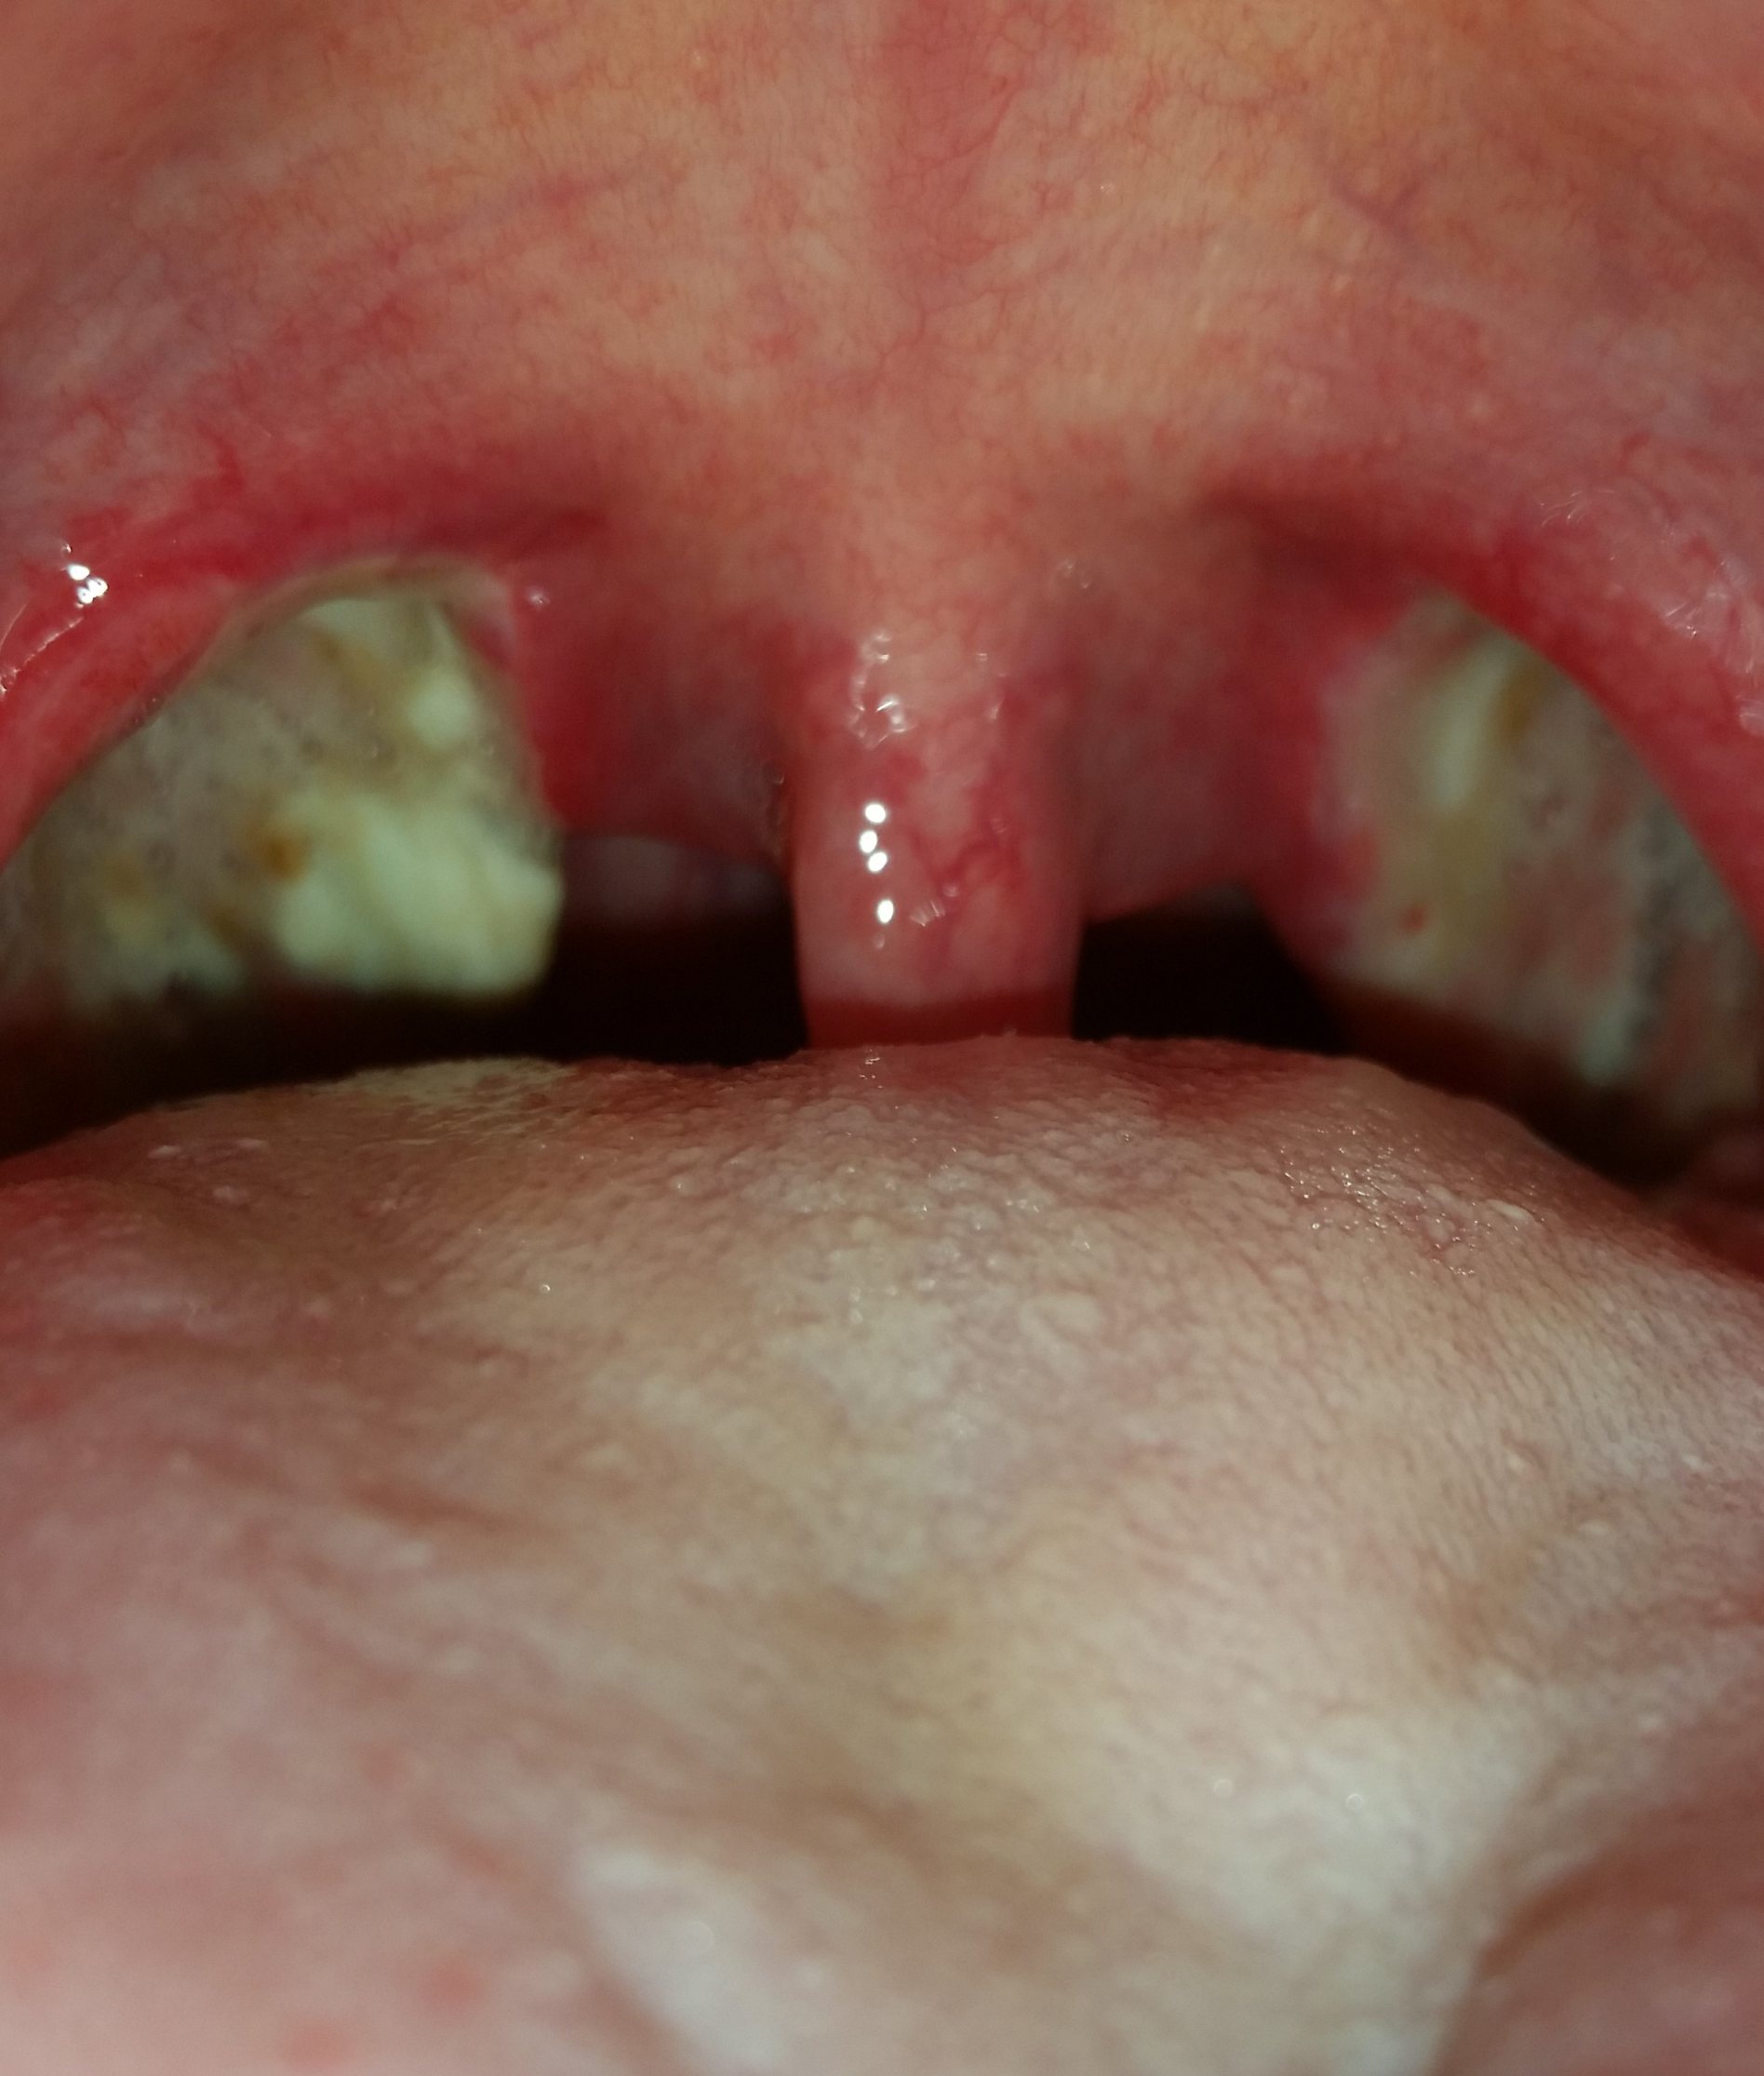

Mandel OP – Bilder Dokumentation Heilungsprozess

- Mandeloperation Tag 0

Nach der Operation bildeten sich direkt die weiß, grünlichen Beläge (Fibrinbeläge).

In der ersten Nacht erhielt ich aufgrund meines stark geschwollenen Halszäpfchen eine Cortison Infusion. Schmerzen hatte ich größenteils in der Nacht und am Morgen.